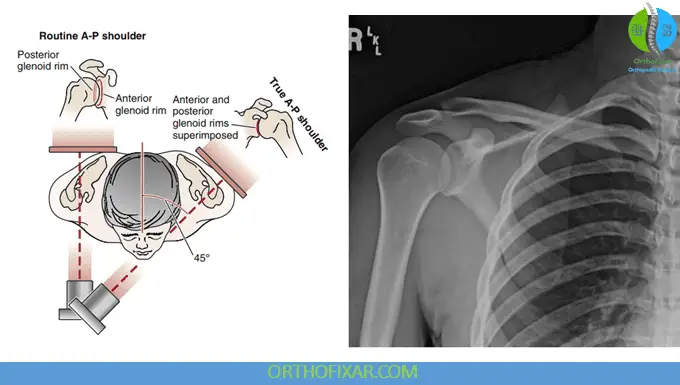

Anteroposterior (AP) View

This projection can be obtained as either a true AP view or a tilt view.